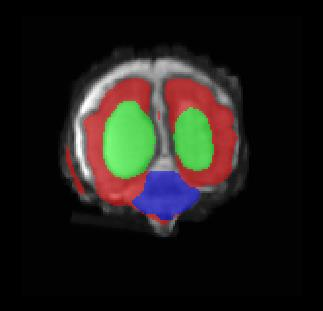

Limiting failures of machine learning systems is of paramount importance for safety-critical applications. In order to improve the robustness of machine learning systems, Distributionally Robust Optimization (DRO) has been proposed as a generalization of Empirical Risk Minimization (ERM). However, its use in deep learning has been severely restricted due to the relative inefficiency of the optimizers available for DRO in comparison to the wide-spread variants of Stochastic Gradient Descent (SGD) optimizers for ERM. We propose SGD with hardness weighted sampling, a principled and efficient optimization method for DRO in machine learning that is particularly suited in the context of deep learning. Similar to a hard example mining strategy in practice, the proposed algorithm is straightforward to implement and computationally as efficient as SGD-based optimizers used for deep learning, requiring minimal overhead computation. In contrast to typical ad hoc hard mining approaches, we prove the convergence of our DRO algorithm for over-parameterized deep learning networks with ReLU activation and a finite number of layers and parameters. Our experiments on fetal brain 3D MRI segmentation and brain tumor segmentation in MRI demonstrate the feasibility and the usefulness of our approach. Using our hardness weighted sampling for training a state-of-the-art deep learning pipeline leads to improved robustness to anatomical variabilities in automatic fetal brain 3D MRI segmentation using deep learning and to improved robustness to the image protocol variations in brain tumor segmentation. Our code is available at https://github.com/LucasFidon/HardnessWeightedSampler.